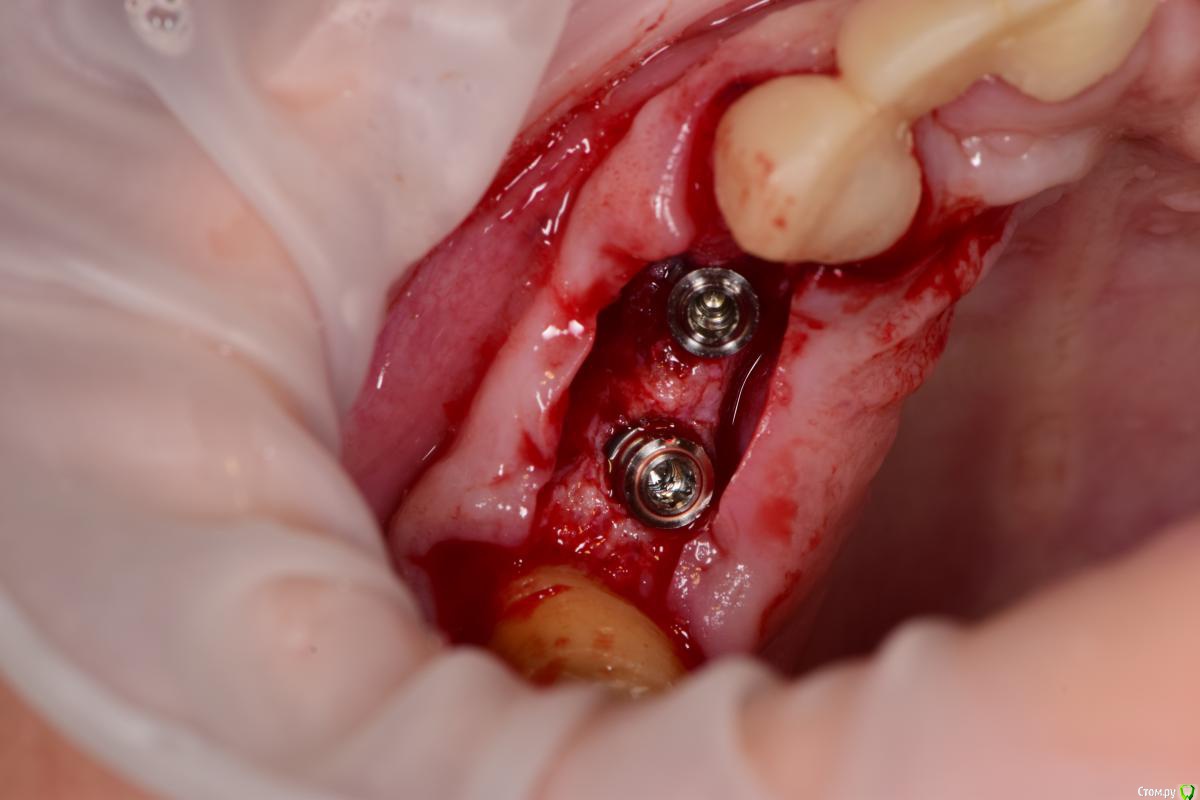

Петр Бриньковский Опубликовано 20 мая, 2017 Поделиться Опубликовано 20 мая, 2017 Южнокорейские импланты с использованием спейсеров и прикручиваемых титановых сеток при НКРзалесных ренген.bmp 4 Ссылка на комментарий

Петр Бриньковский Опубликовано 21 мая, 2017 Автор Поделиться Опубликовано 21 мая, 2017 (изменено) Чем сетки покрывали? Почему выбрали этот метод?PRF мембраны, метод работает достаточно неплохо , в последнее время очень часто так делаю после того как в Корею осенью к доктору Паку на конференцию съездил. Сетки разных форм и ширины и с помощью спейсеров можно увеличиваться немного по высоте(1-3 мм). Каркас достаточно надежный и впоследствии достаточно легко удаляются без сильного отслоения, а на сами спейсеры прикручивается дополнительно формик(можно одномоментно). Изменено 21 мая, 2017 пользователем Петр Бриньковский Ссылка на комментарий

Петр Бриньковский Опубликовано 21 мая, 2017 Автор Поделиться Опубликовано 21 мая, 2017 а что под сетки?и где забор?(если только ауто)Под сетки "Mega-Oss" и поверх мембраны PRF Ссылка на комментарий

Петр Бриньковский Опубликовано 22 мая, 2017 Автор Поделиться Опубликовано 22 мая, 2017 Синий имплантат похож на учебный осстем. Что за фирма?Это синее покрытие имплантов Mega Gen, в данном случае Ayn One Ссылка на комментарий